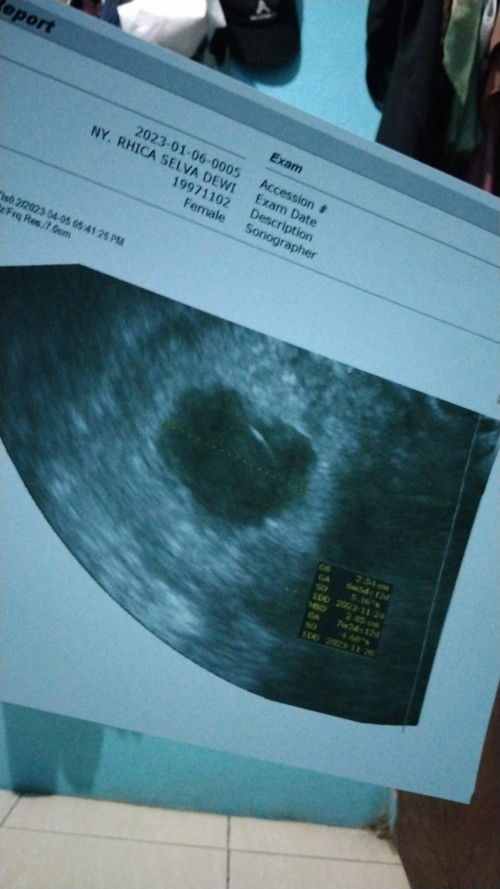

Ibu hamil

Bund, aku hamil 11w tpi janinnya blm terlihat masih kantong aja,normal ga bund?

Hamil 11 w